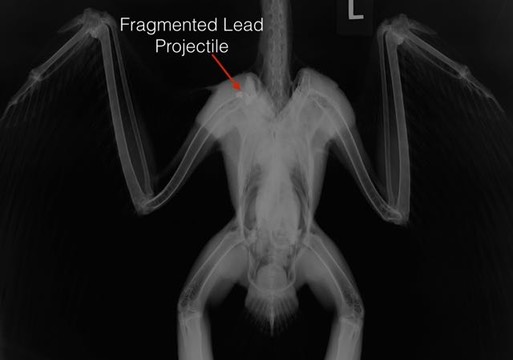

Red-tailed Hawk 18-003

A juvenile Red-tailed Hawk was found in Columbia Park, Kennewick, WA, unable to fly. A radiograph showed that she had been shot. Her shoulder was too badly damaged to be repaired. To make matters even worse, she had a toxic level of lead in her blood, 21 micrograms/deciliter. In addition to being shot, she had eaten another animal that had also been shot.